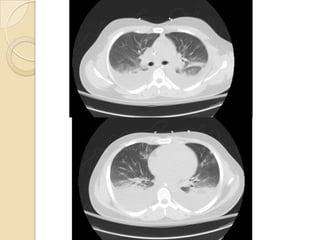

 High resolution CT ground-glass

attenuation, airspace consolidation,

poorly defined nodules.

 The triad of

• Interlobular septal thickening,

• Bronchovascular bundle thickening,

and

• Pleural effusions

are most suggestive AEP

Imaging  High resolutionCT ground-glass attenuation, airspace consolidation, poorly defined nodules.  The triad of • Interlobular septal thickening, • Bronchovascular bundle thickening, and • Pleural effusions are most suggestive AEP